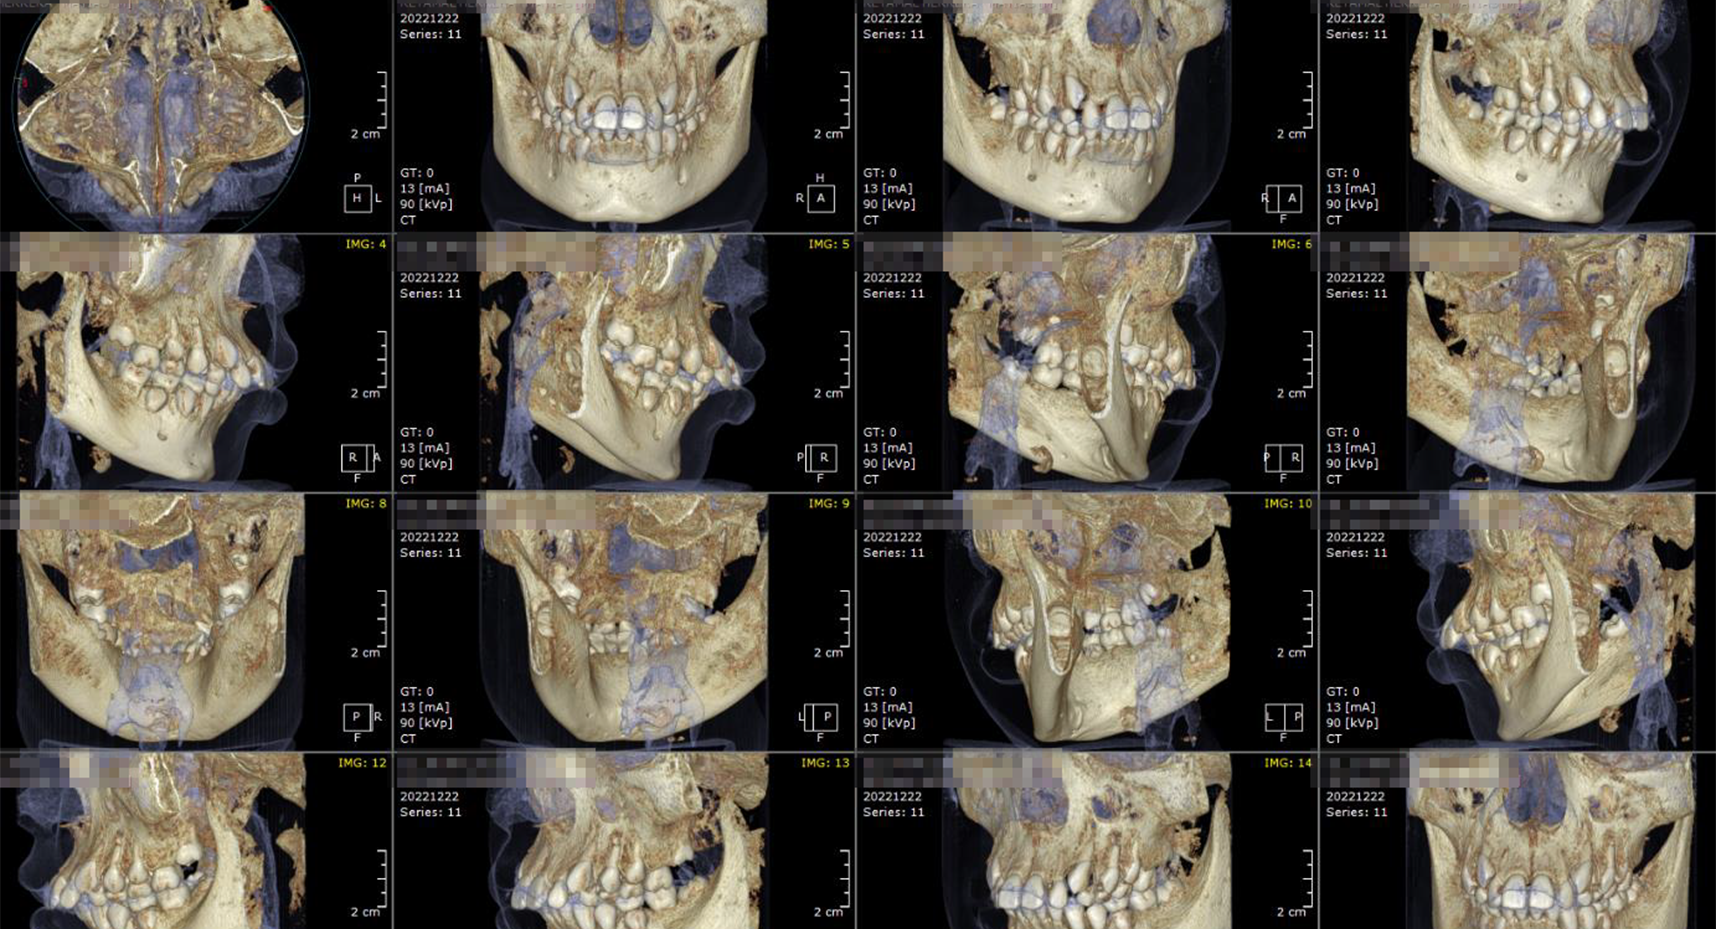

Evaluación Implantes:

Maxilar/ Mandibular/ Bimaxilar/ Orbitomaxilofacial

Estudio Localización:

Traumatismo/ Patología Ósea

Estudio Endodoncia Diente (S)

Estudio Ortodoncia:

Incluye Reconstrucción Panorámica, Telerradiografía 3D Lateral y Frontal; Modelos Oclusión 3D, ATM Bilateral y Vía Aérea Superior 3D